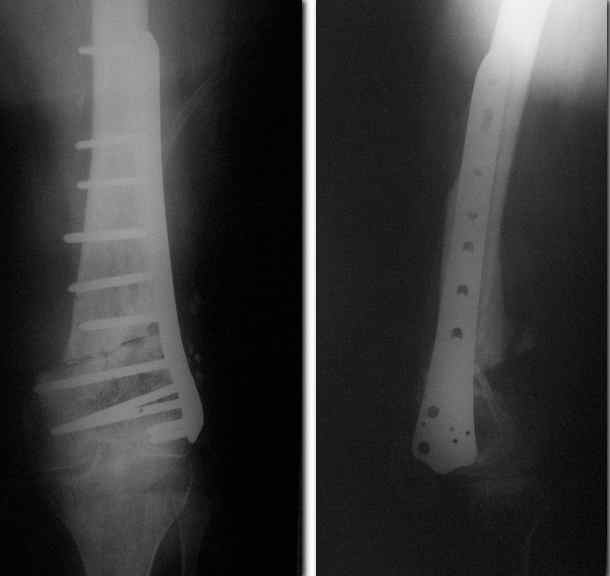

Пример подобного ложного сустава в приложении.

На сегодня есть имплантаты с куда более продвинутой дистальной фиксацией.

Спасибо. Прооперировали во вторник.

Выглядит красиво. А движения в колене какие были на столе?

Была контрактура и спаянный с суставной поверхностью надколенник. Сделали до синтеза редрессацию. Достигли почти полного объема движений.